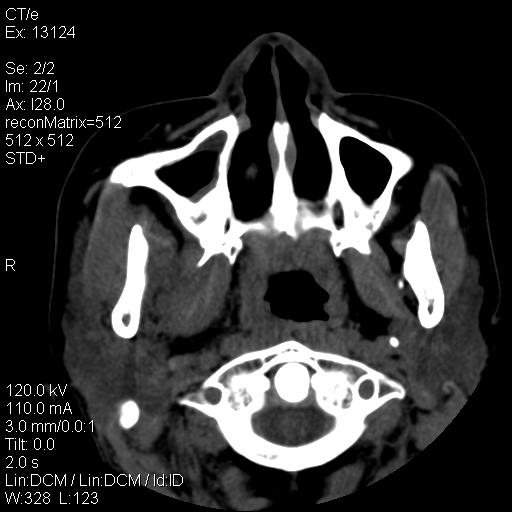

标题: CT18257:女,29岁,右下磨牙痛 [打印本页]

标题: CT18257:女,29岁,右下磨牙痛

女,29岁,右下磨牙痛,因产后2月,故未治疗。现右颌肿痛伴张口困难。请大家看看右侧鼻咽部、口咽部是否

考虑线样体肥大,请鼻镜协查。

2.右侧上颌窦炎症、两侧下鼻甲肿大

1)考虑右侧下颌区软组织脓肿(牙源性)。2)鼻咽部炎性改变;建议追踪复查。3)右侧上颌窦炎。4)双侧下鼻甲黏膜肥厚。

1)考虑右侧下颌区牙源性软组织脓肿。2)右侧上颌窦炎。3)双侧下鼻甲黏膜肥厚。4)鼻咽部炎性改变;建议追踪复查。